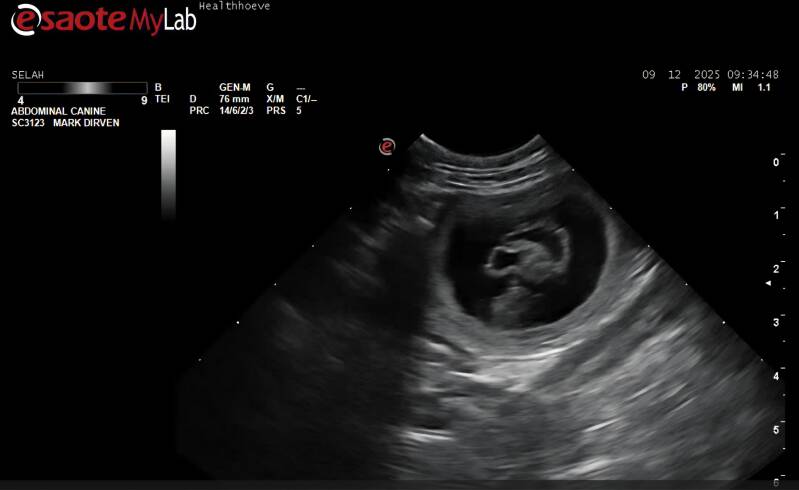

- 9 december 2025

Pups Verwacht!

januari 2026

Heel mooi nieuws:

De echo heeft bevestigd dat Selah drachtig is. We kijken er naar uit dat Selah en Gijs binnenkort ouders zullen worden van een prachtig stel nieuwe witte wondertjes!

De pups worden de tweede week van januari 2026 verwacht.